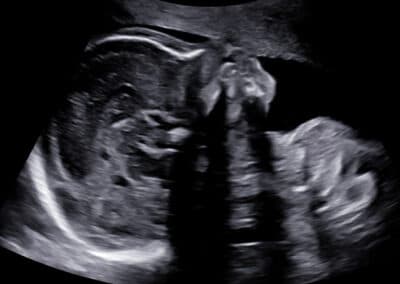

Vyšetření profilu obličeje

Vyšetření páteře

Vyšetření ručičky

Ultrazvukové vyšetření provádíme přes břišní stěnu. Močový měchýř maminky nemusí být naplněný, protože miminko již není v pánvi ale v dutině břišní. Určíme uložení a stav placenty, množství plodové vody a počet cév v pupečníku. Změříme příčný průměr a obvod hlavičky, obvod bříška, délku stehenní kosti a podrobně vyšetříme všechny orgány miminka. Pokud si budete přát znát pohlaví miminka, rádi vám jej sdělíme. Budete-li si chtít připojit 3D-4D ultrazvukové vyšetření s reálným zobrazením vzhledu miminka , připojíme jej. Při vyšetření se řídíme zásadami Fetal Medicine Foundation a všichni lékaři mají FMF certifikát na ultrazvukové vyšetření miminka ve 2. trimestru .